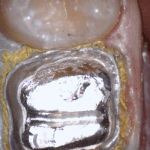

An old PFM crown warranted replacement due to open margins and recurrent decay. After the crown was removed, the margins were refined and the tissue was displaced with expasyl and retraction cord.

This video is deliberately captured slowly so a new user can appreciate how to hold the camera to capture the margins and the contacts of the adjacent teeth. You also have the opportunity to place your own margins and the path of draw before submit the case to the lab.